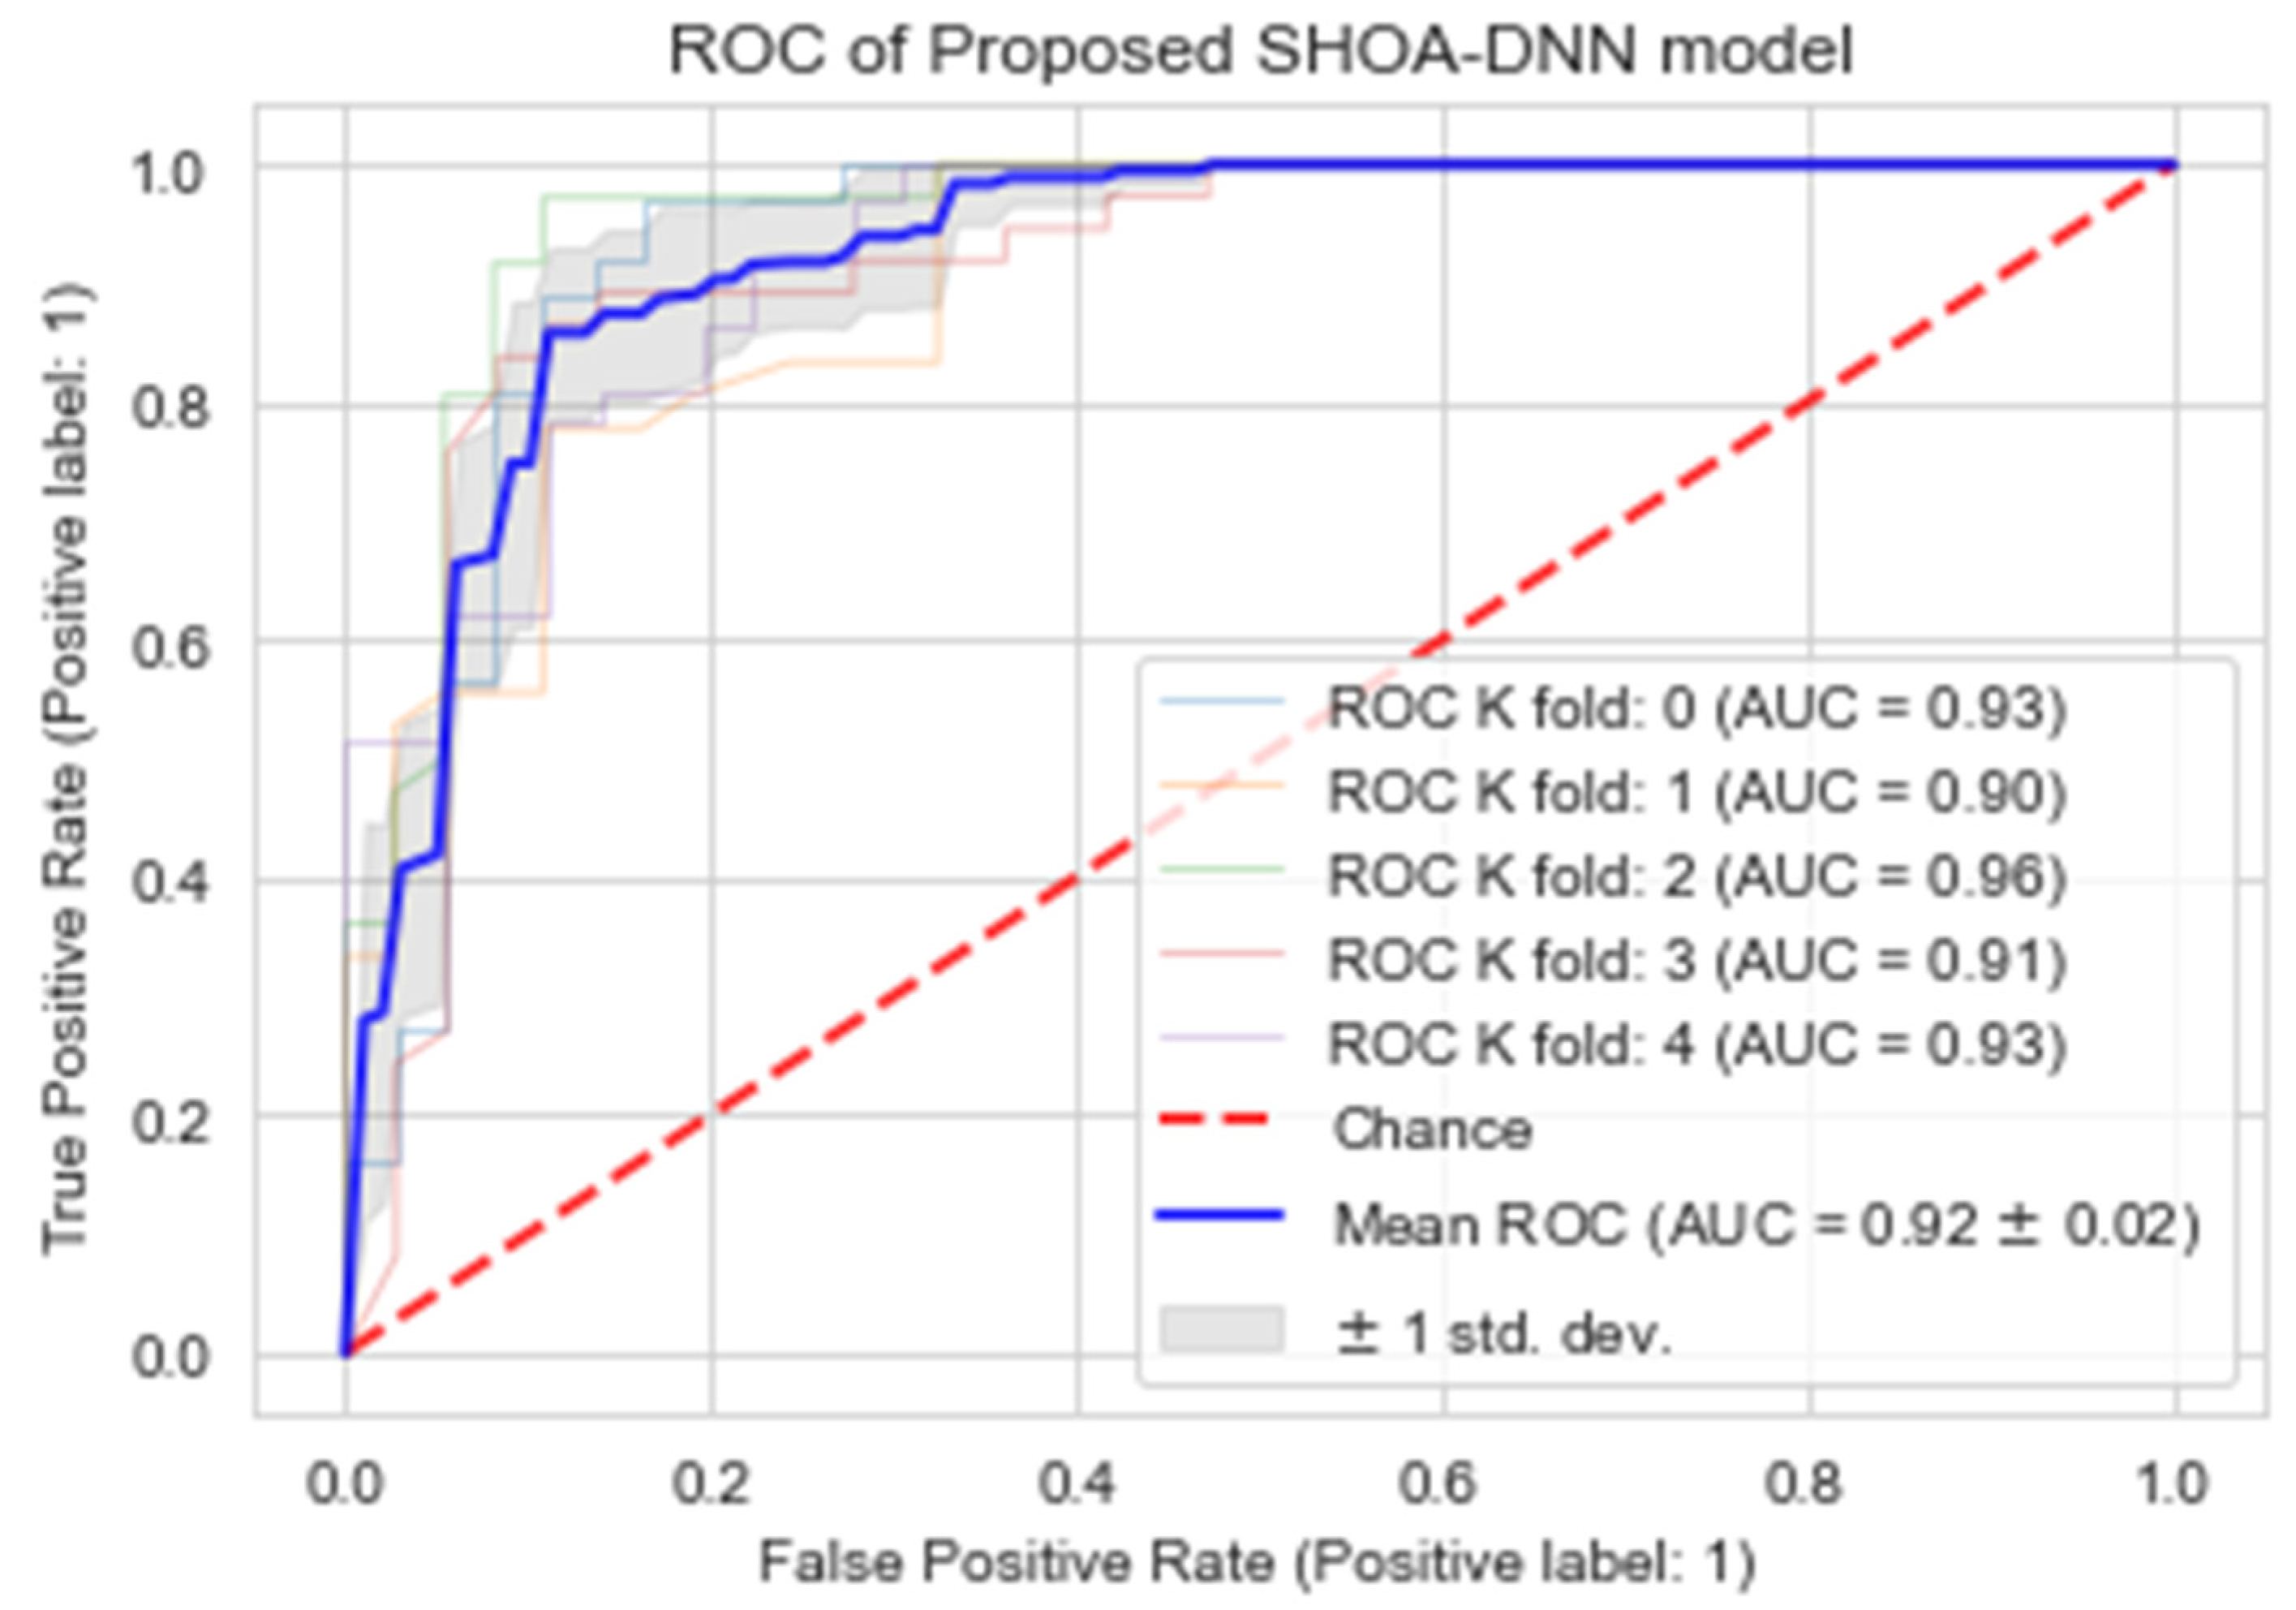

4.4. Performance Evaluation of the Proposed SHOA-DNN Using Cross-Validation

| CV1 | Accuracy (%) | Recall (%) | Specificity (%) | MCC (%) |

|---|---|---|---|---|

| K = 1 | 0.93 | 95.82 | 90.10 | 0.91 |

| K = 2 | 0.90 | 98.35 | 88.56 | 0.87 |

| K = 3 | 0.96 | 97.01 | 92.14 | 0.94 |

| K = 4 | 0.91 | 89.25 | 100.00 | 0.88 |

| K = 5 | 0.93 | 91.55 | 96.33 | 0.92 |

| Mean | 0.92 | 94.39 | 93.42 | 0.91 |